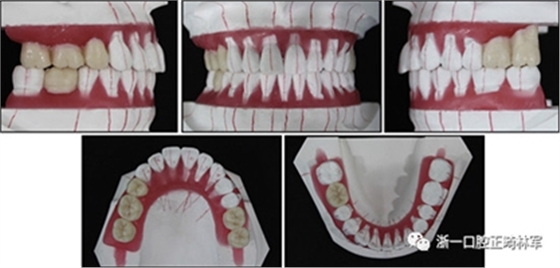

完成診斷性設(shè)計后,治療后穩(wěn)定的咬合是確定的(圖5)。進行治療之前,治療計劃和順序需要通過涉及正畸,牙周病和修復(fù)的多學(xué)科綜合治療方法加以確認(rèn)(圖6)。牙周治療應(yīng)在正畸治療前完成。牙周疾病的治療采用全口潔治,上頜和下頜前牙區(qū)的刮治術(shù),以及下頜左側(cè)后牙區(qū)的翻瓣手術(shù)。休息3個月后,幾乎每個部位都實現(xiàn)了牙周袋深度縮小,探針出血幾乎沒有(表III)??刂蒲装Y后,開始正畸治療。在正畸治療期間定期進行牙周維護的復(fù)診檢查。

圖5. 治療計劃的診斷性設(shè)置

圖6. 治療計劃和應(yīng)用正畸學(xué),牙周學(xué)和修復(fù)學(xué)的跨學(xué)科綜合治療順序